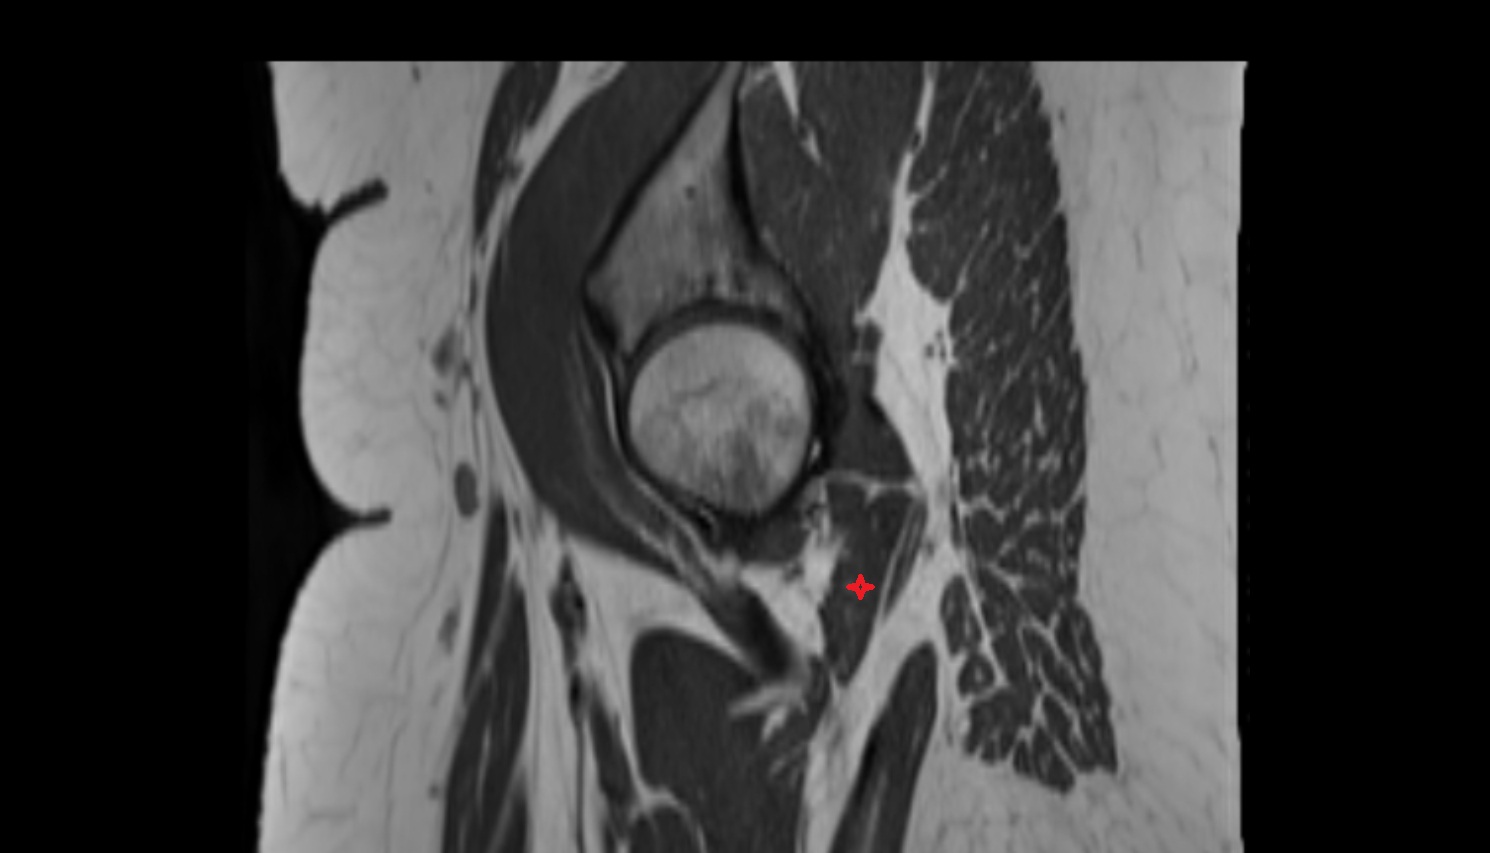

- Hip joint